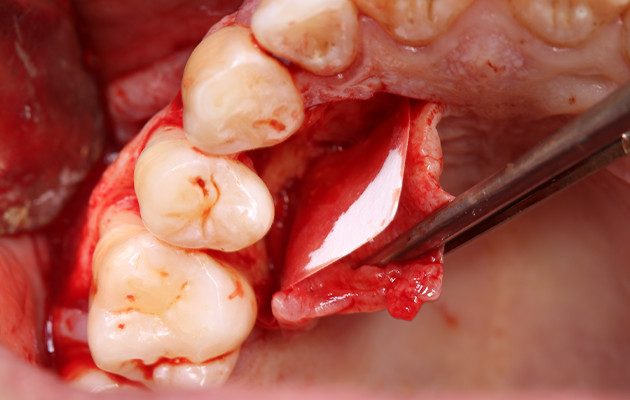

6 e 7 | Descolamento vestibular e janela de acesso à lesão.

8 e 9 | Acesso palatino e início da enucleação.